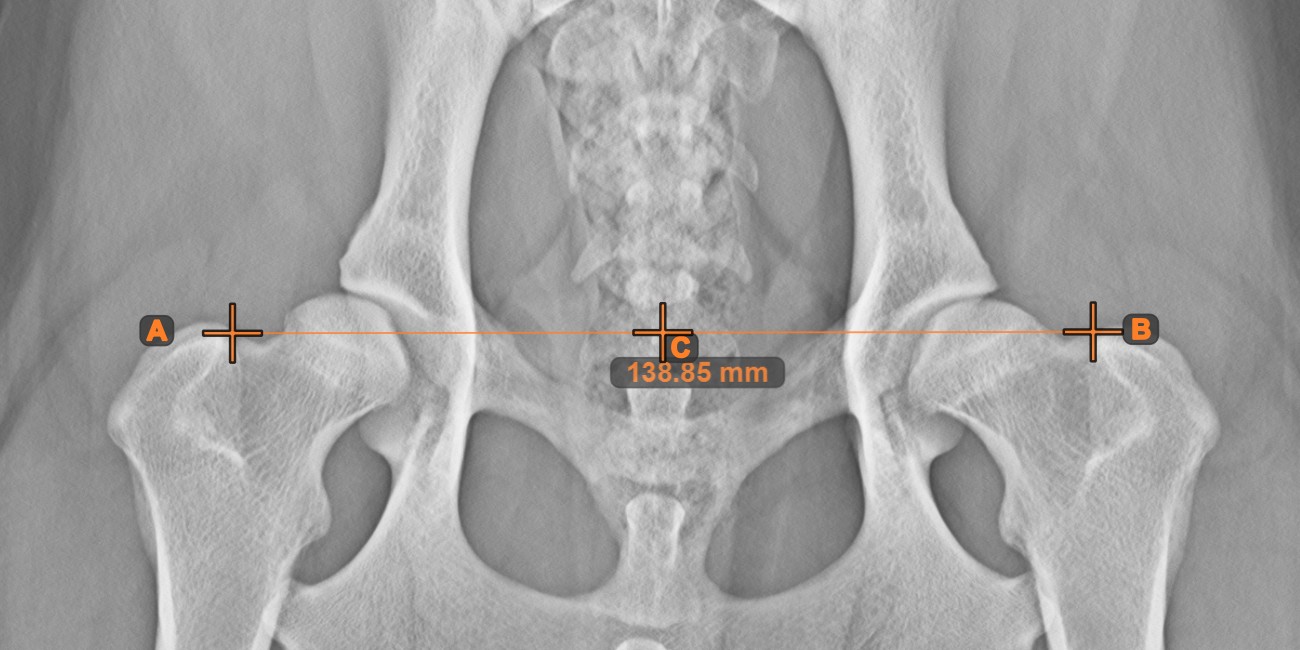

Center Point of Line

Identify and mark the center point of a new or existing line measurement on the scene by using the Center Point of Line tool.

Select the tool from the left toolbar and assign it to one of the available mouse buttons. Place the start and end points on the scene, select them from already existing points on the image, or select an already drawn line from the scene. The center point of the line will be automatically calculated and placed on the scene. The center point of each line will always be marked with the letter C.

../_images/image284.jpg